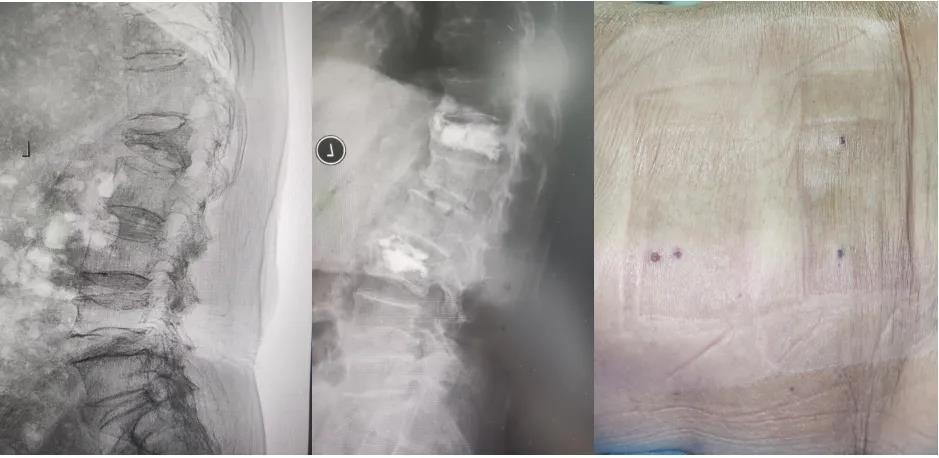

经皮椎体后凸成形术(PKP)

针对老年骨质疏松性椎体压缩骨折,科室广泛开展PKP手术。通过向塌陷的椎体内注入骨水泥,快速稳定椎体,恢复椎体高度,有效缓解疼痛,使患者能在术后短期内下床活动,避免了长期卧床带来的系列并发症。